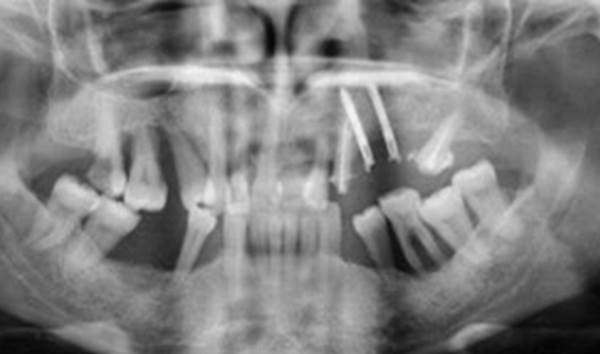

Clinical case: Full-mouth implants for mandibular & maxilla - restored using mixed prostheses

- Courtesy of Dr. Hyun Jun Kim, Korea -

Keywords

AnyRidge, full-mouth implants, mandibular, maxilla, edentulous, full mouth rehabilitation, Octa abutment, long-term clinical case, biological stability, Dr. Hyung Jun Kim